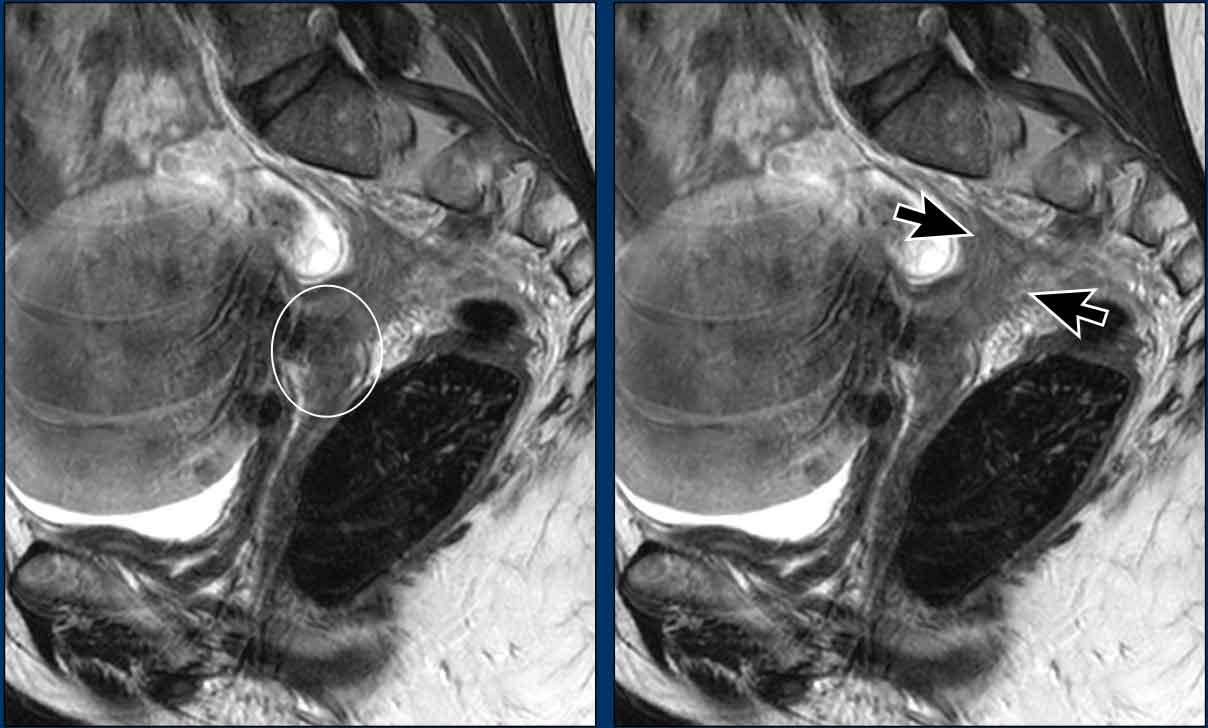

Hình ảnh

Có ung thư cổ tử cung tiến triển tại chỗ với xâm lấn cạnh cổ tử cung và thành bên chậu hông bên phải.

Có một hạch 7 mm ở mặt sau tĩnh mạch chậu ngoài phải (mũi tên trắng) không xác định được trên MRI.

Dựa vào kích thước, hạch này không rõ ràng là bệnh lý.

Trên PET/CT tương ứng, khối u nguyên phát bắt FDG rõ ràng, cũng như hạch cạnh chậu nhỏ (mũi tên đen), qua đó chẩn đoán là N+.